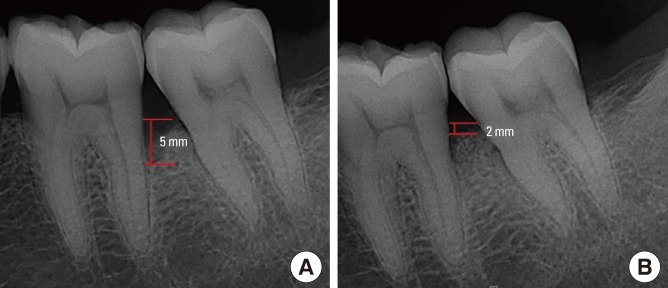

Le Cliché Rétro-Alvéolaire : L’Examen de Référence

Dans le cas des lésions infra-osseuses, la radiographie permet d’analyser la zone interproximale ainsi que la morphologie radiculaire. Le cliché rétro-alvéolaire (ou rétro-coronaire), réalisé avec un angulateur (technique du parallélisme), est l’examen de référence.

Il assure un strict parallélisme du film radiographique par rapport au grand axe de la dent, minimisant les déformations géométriques et permettant une évaluation fiable de la hauteur osseuse et de la morphologie de la lésion.

Supériorité sur l’Orthopantomogramme

L’orthopantomogramme (OPG ou panoramique dentaire) est nettement moins précis en raison des nombreuses déformations géométriques générées par ce type d’examen. Une étude de référence de Pepelassi et coll. (1997) a clairement établi que le clinicien avait quatre fois plus de chance de détecter des LIO à partir d’une lecture de clichés rétro-alvéolaires qu’à partir d’une lecture d’un orthopantomogramme.

Problématique identifiée : Sondage révèle un cratère osseux interdentaire de 5 mm entre 46 et 47 (deux premières et deuxièmes molaires mandibulaires droites). La sonde passant facilement en vestibulo-lingual confirme la destruction des deux corticales (lésion à deux parois — cratère). Mobilité de classe I sur la 46. OPG confirmé par cliché rétro-alvéolaire.